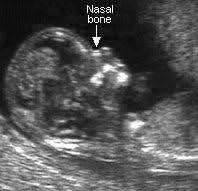

Examples Of Nasal Bone Length And Prenasal Thickness Measurements Download Scientific Diagram

Fetal Facial Profile Markers Of Down Syndrome In The Second And Third Trimesters Of Pregnancy Vos 2015 Ultrasound In Obstetrics Amp Gynecology Wiley Online Library